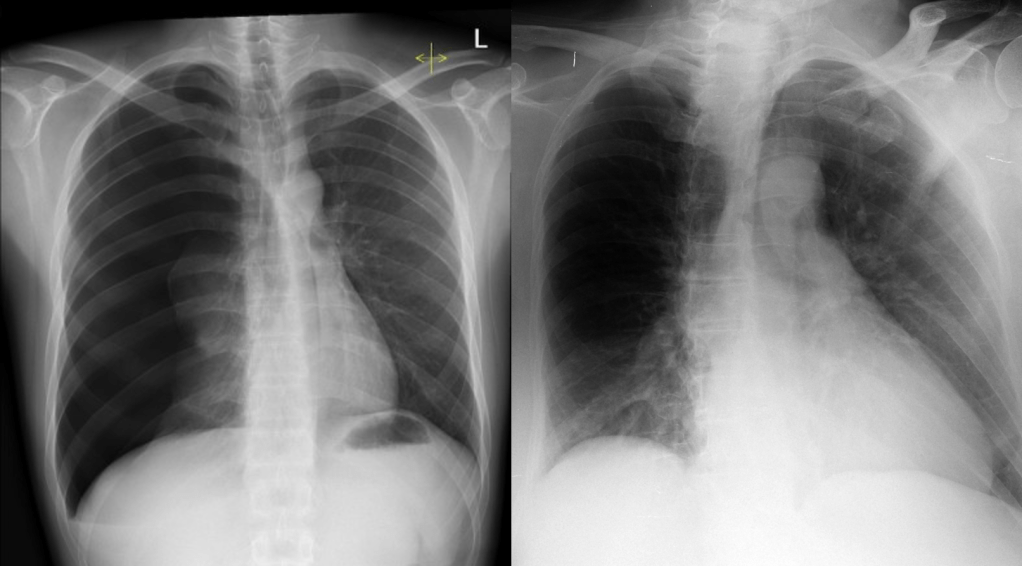

Alright. So, deep breath. An AI company has been cleared to sell an autonomous AI system that reads chest x-rays and, for at least some studies, sends out reports without human oversight*.

In real life, some medical AI systems are very narrow. For example Viz.ai has a very successful product which looks for “large vessel occlusions” – blood clots in the brain that are very consistent in appearance and location – the very definition of a narrow task. Other medical AI systems are more broad, for example annalise.ai** has a chest x-ray interpretation system that looks for 120+ findings on a chest x-ray, many of which are highly variable in appearance and location.

Well, it explicitly can’t diagnose a collapsed lung, or cancer, or a raging chest infection. It has no outputs to tell you if any of these things are present, therefore if you take this risk stratification tool at face value, then by definition it is intended to be used to detect if an x-ray is normal; a condition which is not a serious disease or condition, and is in fact not even a diagnosis at all. By the flowchart, that makes it a Class IIa device (since it is autonomous).

But the AI by Oxipit was regulated as Class IIb in Europe, equivalent to an autonomous system that concerns serious disease and conditions or, if it was not fully autonomous, even potentially life-threatening ones. Why?

I’m sure you have already worked out the trap. By calling the device a normal detector, it makes us think that the model is only responsible for low risk findings. If it makes an error, it has only (incorrectly) decided a normal study might be abnormal, in which case a radiologist reads it as per standard clinical practice. But in reality, there is another sort of error it can make: what happens when it calls a scan normal and it actually contains disease? What sort of risk is there, given that this scan will never be seen by a radiologist?

Well, the opposite of “normal” is not “abnormal” in this context. It is literally anything that can go wrong on an x-ray. That includes non-serious conditions, serious conditions, and potentially fatal conditions. It includes urgent, soon-to-be-fatal conditions, where a wrong answer can lead to death, since those can happen in chest x-rays too.